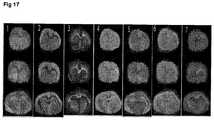

FIG. 17 The effect of mTOR modulation on phosphatidylcholine species in the brain.